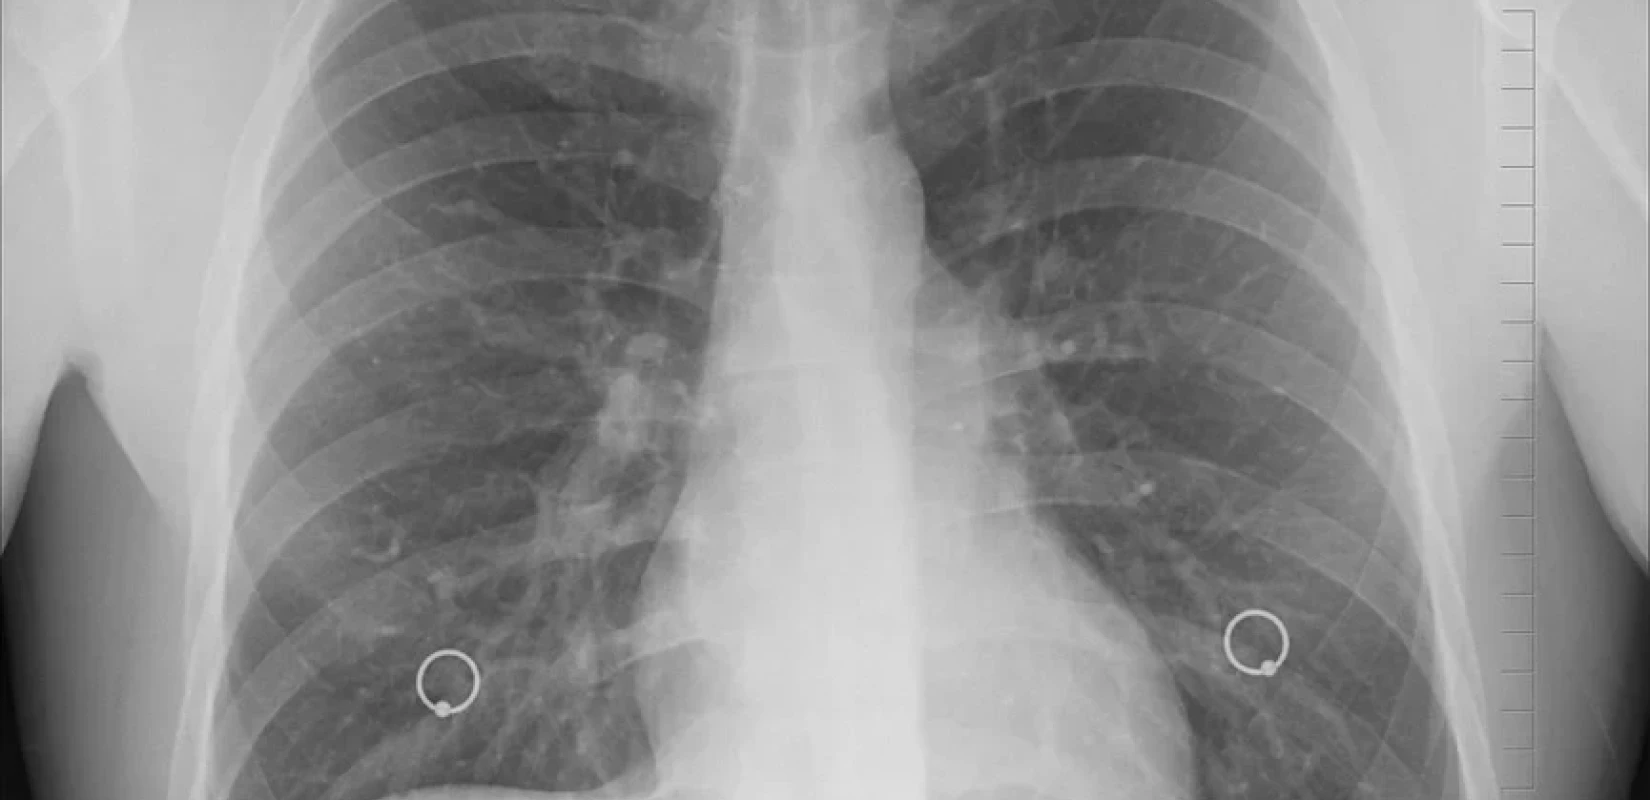

Μία μικρή πόλη χάνεται κάθε χρόνο στην Ευρώπη από καρκίνο του πνεύμονα, που θεωρείται κατά βάση ανδρική ασθένεια, αφού σύμφωνα με τον καθηγητή Πνευμονολογίας στην Ιατρική Σχολή του Πανεπιστημίου Κρήτης και αντιπρόεδρο της Ελληνικής Πνευμονολογικής Εταιρείας Νίκο Τζανάκη, περίπου το 80% των περιπτώσεων παρουσιάζεται σε άντρες και περίπου ένα 20% στις γυναίκες. Όπως δηλώνει ο καθηγητής στο Πρακτορείο Fm και στην εκπομπή της Τάνιας Η. Μαντουβάλου «104,9 ΜΥΣΤΙΚΑ ΥΓΕΙΑΣ», το σύνολο των καρκίνων που καταγράφηκαν το 2020 διεθνώς σε ένα παγκόσμιο Registry, ήταν περίπου 20 εκατομμύρια και προκάλεσαν 10 εκατομμύρια θανάτους. «Από αυτά τα 20 εκατομμύρια τα περίπου δύο εκατομμύρια, το 11.5%, ήταν καρκίνοι του πνεύμονα. Ωστόσο, ενώ οι καρκίνοι του πνεύμονα συμμετέχουν με 11.5% στο συνολικό αριθμό καρκίνων σαν νέες περιπτώσεις, έχουμε περίπου 1,8 θανάτους. Δηλαδή, η θνησιμότητα αγγίζει το 20%. Επομένως, ο καρκίνος του πνεύμονα είναι ένας καρκίνος όχι μόνο συχνός, αλλά και θανατηφόρος. Στην Ευρώπη 500.000 νέα περιστατικά καρκίνου πνεύμονα εμφανίζονται ετησίως και προκαλούνται 385.000 θάνατοι από αυτούς».

Στην Ελλάδα, λέει ο κ. Τζανάκης, έχουμε 10.000 νέα περιστατικά καρκίνου πνεύμονα το χρόνο με μία αναλογία 1 γυναίκα προς 4 άνδρες. «Στο πανεπιστήμιο της Κρήτης από το 1992, έχει οργανωθεί ένα πολύ αξιόπιστο Παγκρήτιο Registry καρκίνου, το οποίο θεωρώ ότι δεν υπάρχει πουθενά αλλού στην Ελλάδα και πιθανότατα είναι ένα από τα ακριβέστερα παγκοσμίως. Το Κέντρο Καταγραφής Καρκίνου Κρήτης δημιουργήθηκε από τον καθηγητή Βλαχονικολή και τώρα διευθύνεται από τον καθηγητή Γενικής Ιατρικής και Πρωτοβάθμιας Φροντίδας Υγείας Χρήστο Λιονή. Μπορούμε να θεωρήσουμε ότι τα δεδομένα του Κέντρου, αντιπροσωπεύουν λίγο και ολόκληρη την Ελλάδα, ίσως με μικρές διαφοροποιήσεις. Είναι ενδεικτικό πάντως ότι το 1992 στην Κρήτη είχαμε 449 νέους καρκίνους, ανά 100.000 κατοίκους. Το 2022, 524 νέα περιστατικά, ανά 100.000 κατοίκους. Δηλαδή αύξηση καρκίνων μέσα σε 30 χρόνια 17% ανεξαρτήτως αιτίας και οργάνου. Και η θνησιμότητα, από 189 θανάτους ανά 100.000 πληθυσμού το 1992, έχει πάει στους 211, ανά εκατό χιλιάδες κατοίκους, τριάντα χρόνια μετά. Ενώ δηλαδή η αύξηση αγγίζει το 17%, η θνησιμότητα παρουσιάζει μία αύξηση 11,6%. Αυτά τα δύο νούμερα αναλογικά, σημαίνουν ότι κάπως καλύτερα αντιμετωπίζουμε τους καρκίνους στο πέρασμα των τριών δεκαετιών. Από όλους αυτούς τους καρκίνους, ο καρκίνος των πνευμόνων αντιπροσωπεύει περίπου το 60-64%, δηλαδή είναι ο συχνότερος. Αμέσως μετά έρχονται κατά σειρά και συχνότητα ο καρκίνος μαστού, προστάτη, παχέoς εντέρου, ήπατος και ενδοηπατικών χοληφόρων, και ουροδόχου κύστεως».

Όσον αφορά το screening για τον καρκίνο του πνεύμονα που ακόμη δεν έχει συμπεριληφθεί στο πρόγραμμα προσυμπτωματικού ελέγχου, παρά το γεγονός ότι είναι από τους συχνότερους και πιο θανατηφόρους καρκίνους, ο καθηγητής λέει ότι θα πρέπει να μπει στο μεγάλο Εθνικό Πρόγραμμα Πρόληψης του Καρκίνου. «Υπάρχουν αντικειμενικές δυσκολίες, γιατί οι μεθοδολογίες που υπάρχουν για αυτή την πρώιμη διάγνωση και την πρόληψη, είναι χρονοβόρες και οικονομικά πάρα πολύ ευαίσθητες. Και αυτή τη στιγμή η ελληνική πνευμονολογική εταιρεία, σε συνεργασία με την Ακτινολογική και Θωρακοχειρουργική Εταιρεία, ετοιμάζει τα κριτήρια, βάσει των οποίων, θα μπει η αξονική χαμηλής ακτινοβολίας στο Εθνικό Πρόγραμμα Πρόληψης. Η ΕΠΕ ετοιμάζεται να προμηθεύσει το δημόσιο και τους εθνικούς φορείς με τα προτεινόμενα κριτήρια για το screening που πρέπει να γίνει σε συγκεκριμένο πληθυσμό. Θα προτείνουμε αυτά τα κριτήρια στο υπουργείο Υγείας, ώστε να αρχίσει πλέον να συστηματοποιείται η πρόληψη και αυτού του πολύ θανατηφόρου καρκίνου και στην Ελλάδα, όπως γίνεται με το μαστό και με άλλους καρκίνους».